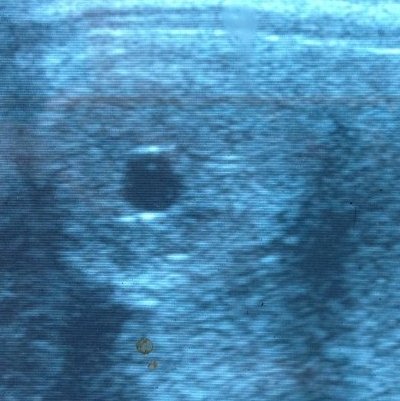

Forårstid er lig med føltid. Både dem der skal komme i år og dem der skal ventes til næste år. Jeg tilbyder min hjælp til alt fra føltjek, inseminering og drægtighedskontrol. Gennem mange år som hingsteejer har jeg stor rutine i at vurdere hopper i brunst. I det daglige har jeg stor glæde af mit makkerskab med Skelgårdens Aslan, der er en meget dygtig og erfaren teaserhingst, som jeg kender særdeles godt. Tilstedeværelsen af en teaserhingst kan være med til at fordoble sandsynligheden for en succesfuld insemination af din hoppe!